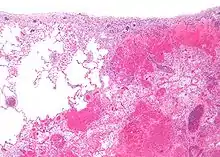

| Micrograph of a pulmonary infarct (right of image) beside relatively normal lung (left of image). H&E stain. | |

- Red infarctions (hemorrhagic infarcts) generally affect the lungs or other loose organs (testis, ovary, small intestines). The occlusion consists more of red blood cells and fibrin strands. Characteristics of red infarcts include: